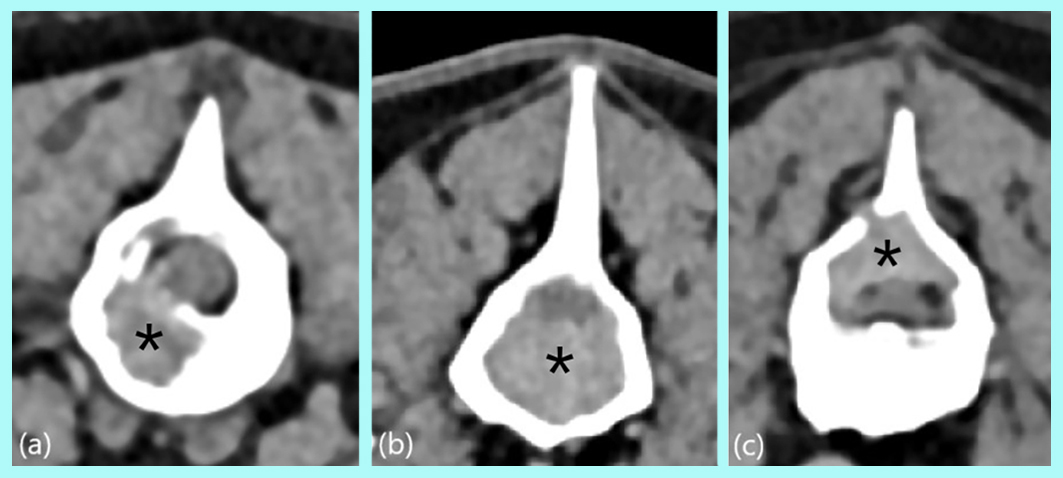

Resumo: O mieloma múltiplo (MM) é uma neoplasia linfoproliferativa rara em cães e gatos. Não há predileção por raça ou sexo e acomete animais na faixa etária de 8 a 14 anos. Os sinais clínicos associados ao MM são inespecíficos e incluem letargia, fraqueza e anorexia. O diagnóstico do MM é baseado na detecção de gamopatia monoclonal no soro ou na urina, lesões osteolíticas por meio de exames de imagem e no aumento de mais de 20% de plasmócitos na medula óssea por meio de citologia aspirativa ou biópsia por fragmento e histopatologia. O tratamento consiste geralmente no uso do melfalano combinado com prednisona que proporciona tempo médio de sobrevivência de 540 dias em cães. Este relato descreve a contribuição da tomografia computadorizada no diagnóstico do mieloma múltiplo em uma cadela, SRD, de 12 anos de idade que apresentava ataxia, fraqueza e redução da propriocepção em membros pélvicos.

Abstract: Multiple myeloma (MM) is a rare lymphoproliferative neoplasm in dogs and cats. There is no predilection for breed or sex and it affects animals between the ages of 8 and 14. The clinical signs associated with MM are non-specific and include lethargy, weakness and anorexia. The diagnosis of MM is based on the detection of monoclonal gammopathy in serum or urine, osteolytic lesions through imaging tests and an increase of more than 20% in plasma cells in the bone marrow through aspiration cytology or a fragment biopsy and histopathology. Treatment usually consists of the use of melphalan combined with prednisone, which provides a mean survival time of 540 days in dogs. This report describes the contribution of computed tomography in the diagnosis of multiple myeloma in a 12-year-old mixed-breed bitch who presented ataxia, weakness and reduced proprioception in the pelvic limbs.